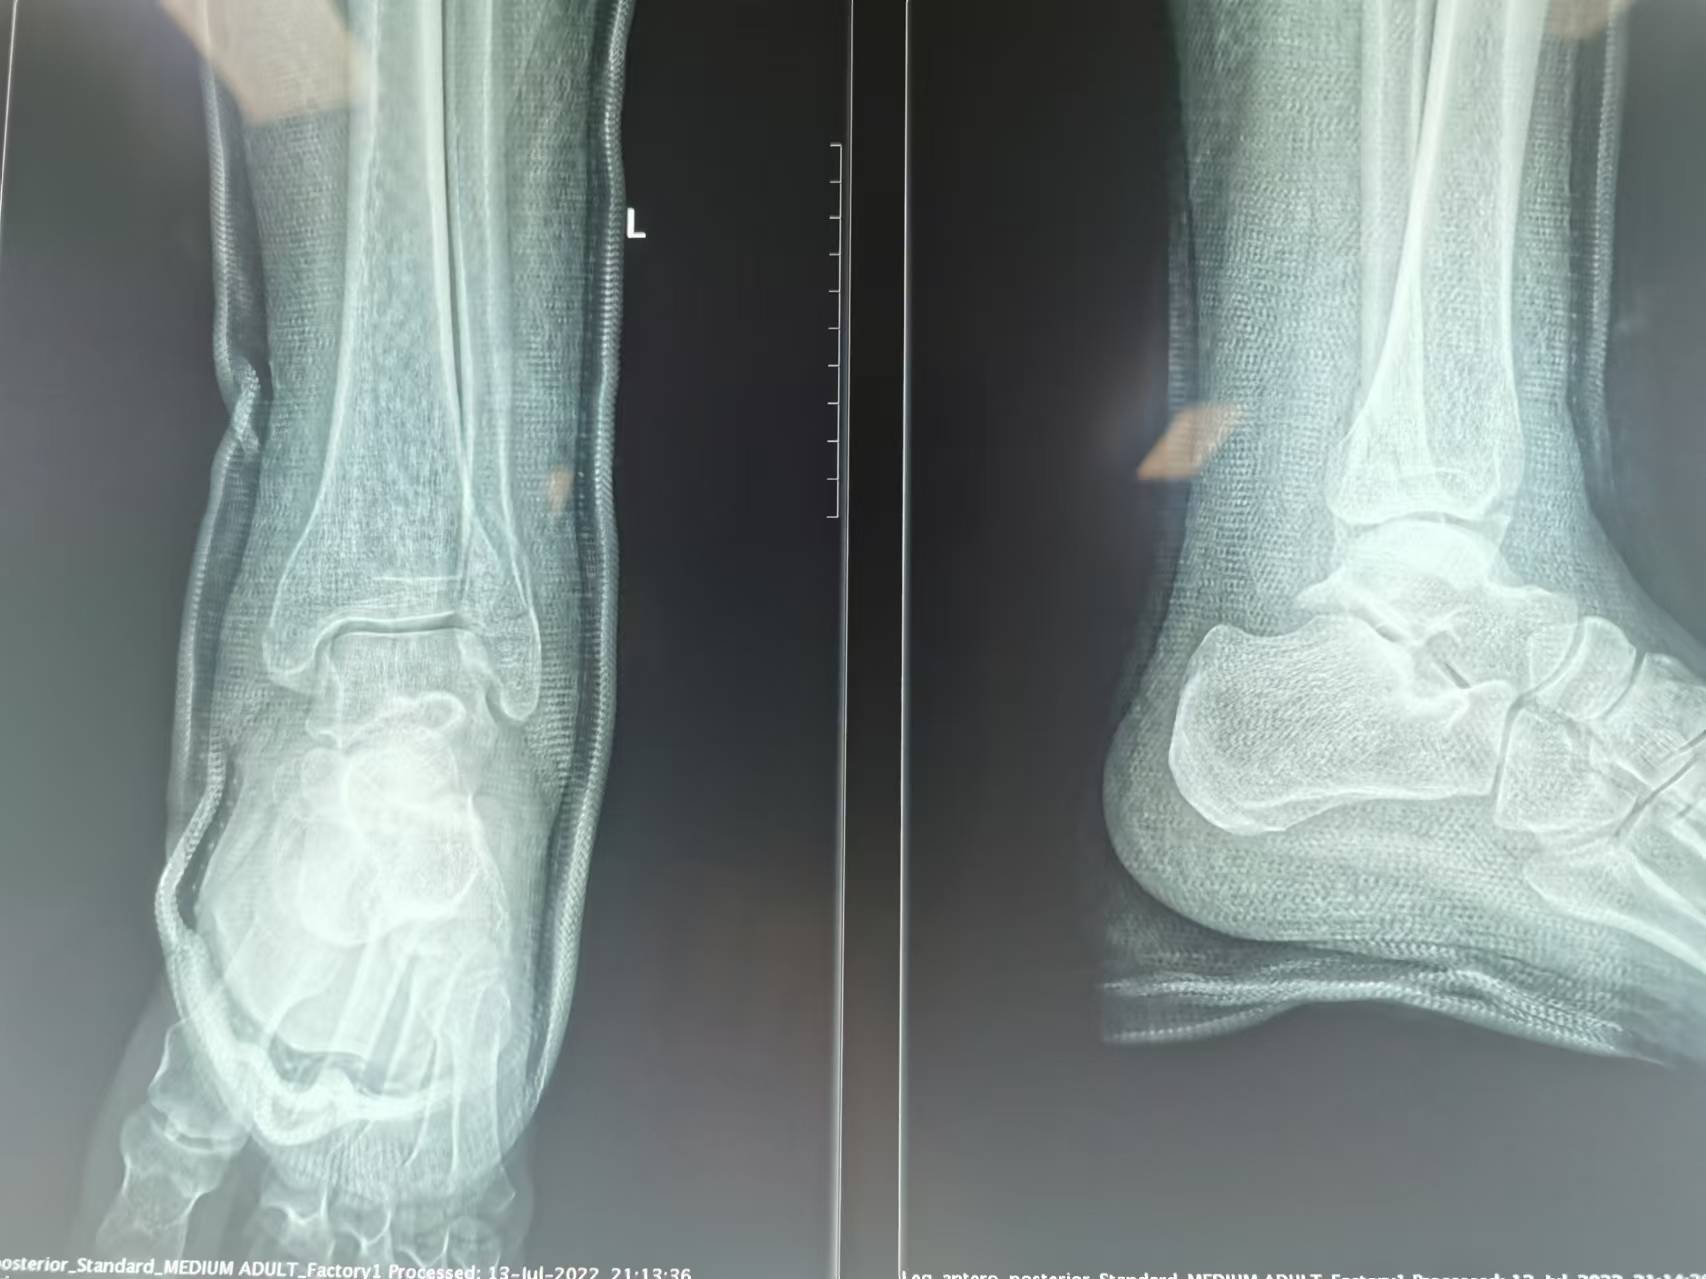

首页 > 张恒云工作室 > 影像资料 四